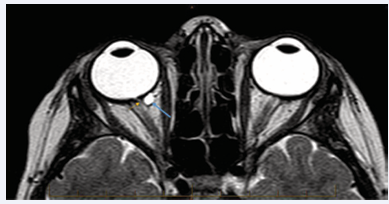

MRI of the brain and orbits was organized to exclude structural abnormalities of the brain and to better visualize optic nerve abnormalities. MRI brain was normal and the optic nerve pit was well-visualized. However, the pit extends in a tubular fashion to form a peripapillary cyst as illustrated in Figure 1.

Figure 1 T2 axial image of the Right optic nerve pit, tubular extension (orange arrow) into a cystic structure which enhances with contrast (blue arrow).

The appearance is distinct from that expected of a morning glory syndrome. The cyst appears to be of 6-7mm in size.